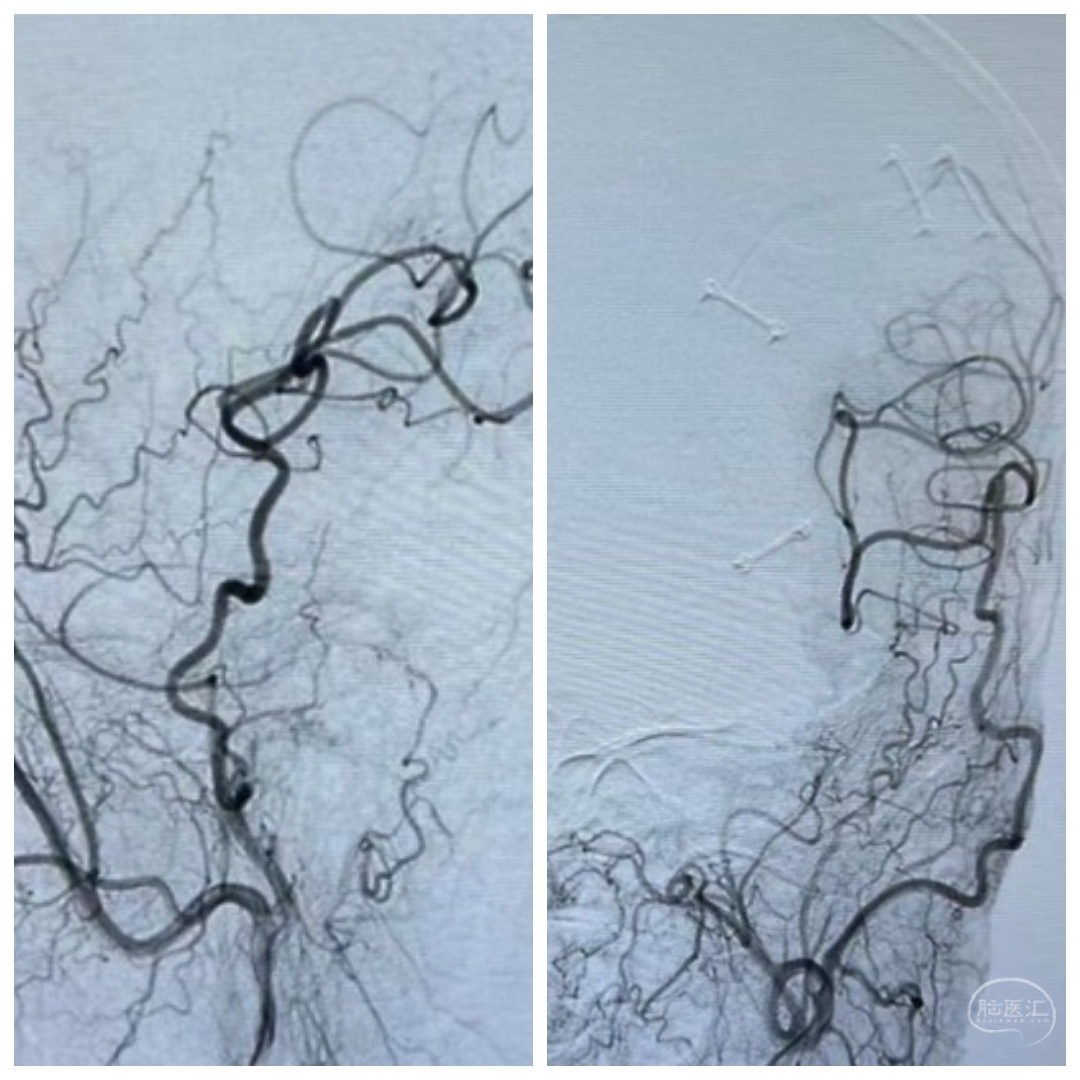

进一步DSA检查提示左侧颈内动脉末端狭窄~果然比MRA精准

予以双导丝双球囊扩张,稀疏的颅内血管终于开枝散叶。术后患者症状改善,治疗效果非常满意。